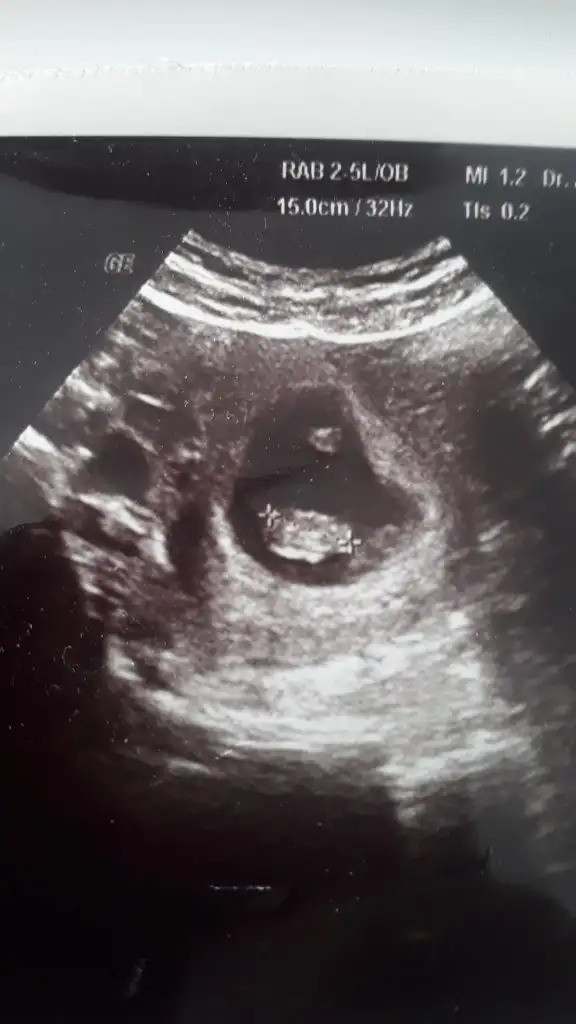

Ya küçük olsa nolcak canim suan kucuk olur zamanla normale döner sagkikli olsun gerisini boswer arkadasiminki onden gidiyodu sonra durdu haftasina gelişimi bi anda inisler cikislar olabilir benimki 6 gun geriden geliodu olabilir dedi doktor suan onemli olam saglikli olmasi dua et takmamaya bak kafana daha kotu olursunKızlar ya benim de pskolojim hiç iyi değil.1 hafta Sonra kontrolum var.Ins gittiğimde kalbini duyarım yine diye dua ediyorum ve çok korkuyorum. Pihtilasma ignemi vuruyorum her gün ama ya yetersiz kalırsa diye kafayı yicem.bir de benim ultrason resminde bebek sizinkilere göre daha küçük sanki.acaba beslenemiyor mu diye korkuyorum sürekli.resmi atayım size burda sata göre 8+3 ama doktor önce 7+2 sonra yok yok 8+1 dedi.sizce haftasına göre küçük mü?

Neden küçük diye düşündün ki normali ne imiş 7+2 de, benim de 6+2 de 0,55 cm idi. Seninkinden anlayamadım kaç cm 1,5 muKızlar ya benim de pskolojim hiç iyi değil.1 hafta Sonra kontrolum var.Ins gittiğimde kalbini duyarım yine diye dua ediyorum ve çok korkuyorum. Pihtilasma ignemi vuruyorum her gün ama ya yetersiz kalırsa diye kafayı yicem.bir de benim ultrason resminde bebek sizinkilere göre daha küçük sanki.acaba beslenemiyor mu diye korkuyorum sürekli.resmi atayım size burda sata göre 8+3 ama doktor önce 7+2 sonra yok yok 8+1 dedi.sizce haftasına göre küçük mü?

1.66 cm yazıyor bunda. 6+4 te 0.87 cm idi.(o zaman 2 gün önde demişti doktor 6+6demisti) Ama sonradan iyi devam etmedi mi diye endişe ediyorum benimle aynı haftada olanlara göre daha küçük gibi geldiNeden küçük diye düşündün ki normali ne imiş 7+2 de, benim de 6+2 de 0,55 cm idi. Seninkinden anlayamadım kaç cm 1,5 mu

7 ve 8 hafta arası için bence gayet sağlıklı boyu1.66 cm yazıyor bunda. 6+4 te 0.87 cm idi.(o zaman 2 gün önde demişti doktor 6+6demisti) Ama sonradan iyi devam etmedi mi diye endişe ediyorum benimle aynı haftada olanlara göre daha küçük gibi geldi